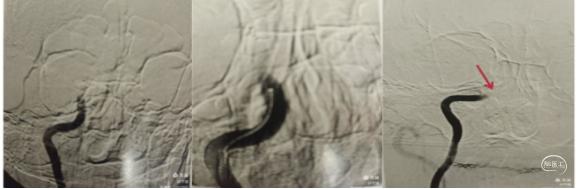

支架取栓联合抽吸:再次将微导丝偿试通过M1段,到达大脑中动脉分叉部分,跟进微导管至分叉部,通过微导管释放4ⅹ20mm取栓支架,静置5分钟,向前跟进微导管,收拢支架,跟进中间导管至M1。边抽拉微导管和支架负压抽吸下将支架拉入中间导管内撤出体外,抽出大量黯红色血栓,支架内抓出黯黑色血栓。

中间导管内造影示大脑中动脉上干、下干通畅,远端血流良好,但上干、下干分叉后血管内仍有发白,考虑仍有血栓或斑块。

再次取栓:再次将支架置于M2段上干,释放支架,跟进中间导管至M1分叉近端,再次取栓和抽吸,取出少量血栓。

取出的大量血栓。